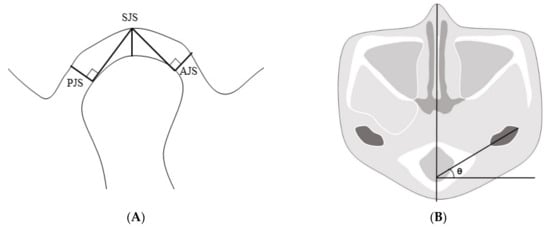

We chose a plane of reference at the left external carotid canal in the axial view, which was a line from the innermost point to the outermost point of the condyle parallel to the sagittal plane. After that, we set a plane perpendicular to the line at its midpoint. The superior joint space (SJS) was defined as the distance measured from the top of the condyle to the deepest point of the glenoid fossa in the plane. Tangent lines were drawn to the most prominent points on the condyle’s anterior and posterior aspects from the deepest point of the glenoid fossa. The anterior joint space (AJS) was defined as the perpendicular distance between the most prominent point on the anterior aspect and the glenoid fossa. The posterior joint space (PJS) was defined as the perpendicular distance between the most prominent point on the posterior aspect and the glenoid fossa. The angle of the condyle or the condylar angle was defined as the angle between the line from the innermost point to the outermost point of the condyle parallel to the sagittal plane and the sagittal plane (Figure 4).

Figure 4.

(A) The plane of reference in the axial plane at the left external carotid canal with lines from the innermost and outermost points on the condyle. Reference plane perpendicular to the line at the midpoint. Anterior, superior, and posterior joint spaces in the plane (AJS, SJS, and PJS, respectively). (B) The angle of the condyle was defined as the angle between the line from the innermost point to the outermost point of the condyle parallel to the sagittal plane and the sagittal plane. AJS: anterior joint space; SJS: superior joint space; PJS: posterior joint space.